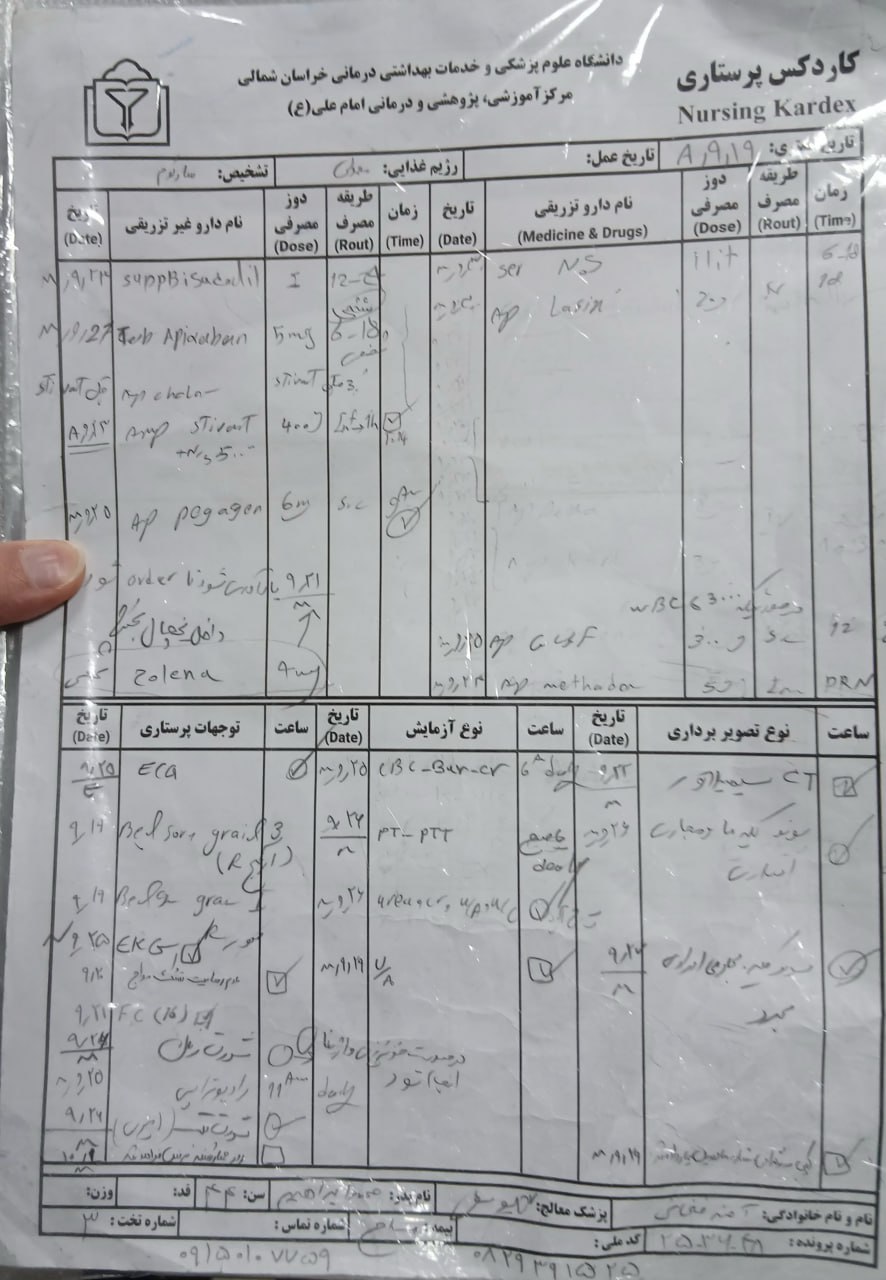

به ترتیب؛ روز ها: ۱۹ آبان, ۲۸ آذر, ۲۹ آذر, ۳۰ آذر

به ترتیب؛ روز ها: ۱۹ آبان, ۲۸ آذر, ۲۹ آذر, ۳۰ آذر

۱۹ آذر

۱۹ آذر

به ترتیب؛ روز ها: ۲۸ آذر, ۲۹ آذر, ۳۰ آذر, ۱ دی

۱ دی